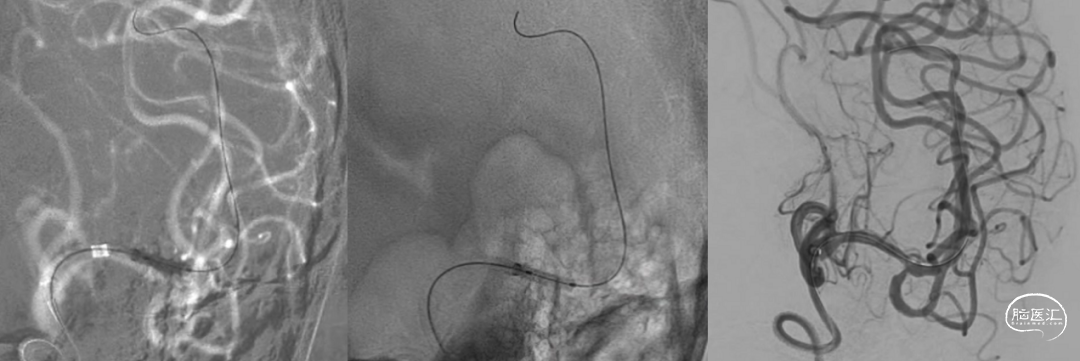

欣维宁10ml静脉推注、6ml/h泵注20min,使用Wingspan 2.5mm×15mm颅内动脉支架定位于残余狭窄段释放。

推送加奇SacSpeed® 2mm×9mm颅内球囊至支架内后扩张成形(加奇SacSpeed® 2mm×9mm颅内球囊内加压至12atm)。

最后造影显示支架贴壁良好、支架内血运通畅、支架以远各级动脉分支显影良好。